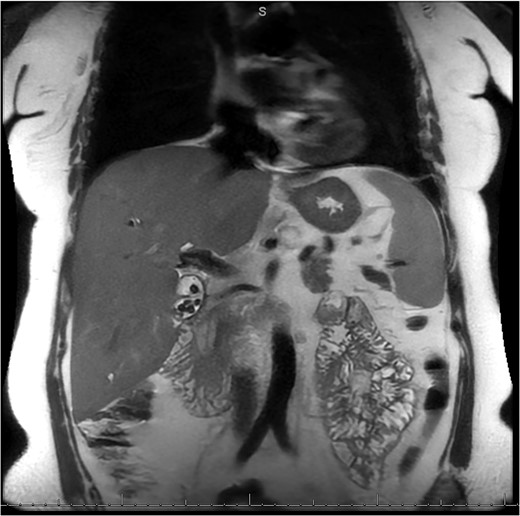

A 49-year-old female with a history of ADPKD and multiple liver cysts, 13-months status post subtotal cholecystectomy, endoscopic retrograde cholangiopancreatography with biliary sphincterotomy and balloon stone extraction, presented to the emergency department with fever and a 4-day history of discomfort in the right upper quadrant. At the time of the initial cholecystectomy, total cholecystectomy could not be performed due to extensive adhesions, and subtotal cholecystectomy with complete evacuation of the stones was done instead. Magnetic resonance cholangiopancreatography (MRCP) done at that time showed a dilated common bile duct (CBD) to 1.5 cm, intra and extrahepatic biliary dilatation, multiple liver cysts measuring up to 2 cm, and multiple stones in the CBD, including at the level of the ampulla (Fig. 1). Computerized tomography scan at the time of the second admission showed acute cholecystitis and she had mildly elevated transaminases, but there was no evidence of cholestasis or pancreatitis. MRCP showed minor proximal intrahepatic biliary dilation and cholelithiasis but no duct calculi (Figs 2–4). A laparoscopic cholecystectomy was attempted with extensive adhesiolysis between the gallbladder and surrounding omentum and mesocolon, but the cystic duct could not be isolated, and ultimately the cased was converted to open. While removing the gallbladder in a top-down fashion, a small bile leak was identified right at the closed end of the gallbladder remnant, where the bile duct was adhered to the gallbladder wall. Intraoperative cholangiogram was obtained through a small perforation in a right posterior bile duct at the site of attachment, which showed right posterior, right anterior and left hepatic ducts of equal size converged at a trifurcation (Fig. 5). The duct was repaired over a T-tube and observed throughout the rest of the case and no bile leak was identified. The gallbladder was opened along its lateral edge, revealing a hugely dilated cystic duct with ~10 to 12 marble-sized stones packed within the gallbladder remnant and cystic duct down to the juncture with the common bile duct. All the stones were removed and the safe portion of the gallbladder remnant was resected leaving the side attached to the bile duct in situ due to the Mirizzi anatomical variant. The cystic duct was oversewn along with the remnant of the gallbladder wall. Pathology showed acute-on-chronic cholecystitis with cholelithiasis. Repeat MRCP showed no retained stones in the biliary tree. The recovery course was unremarkable.

MRI/MRCP from second hospitalization demonstrating recurrent cholelithiasis.